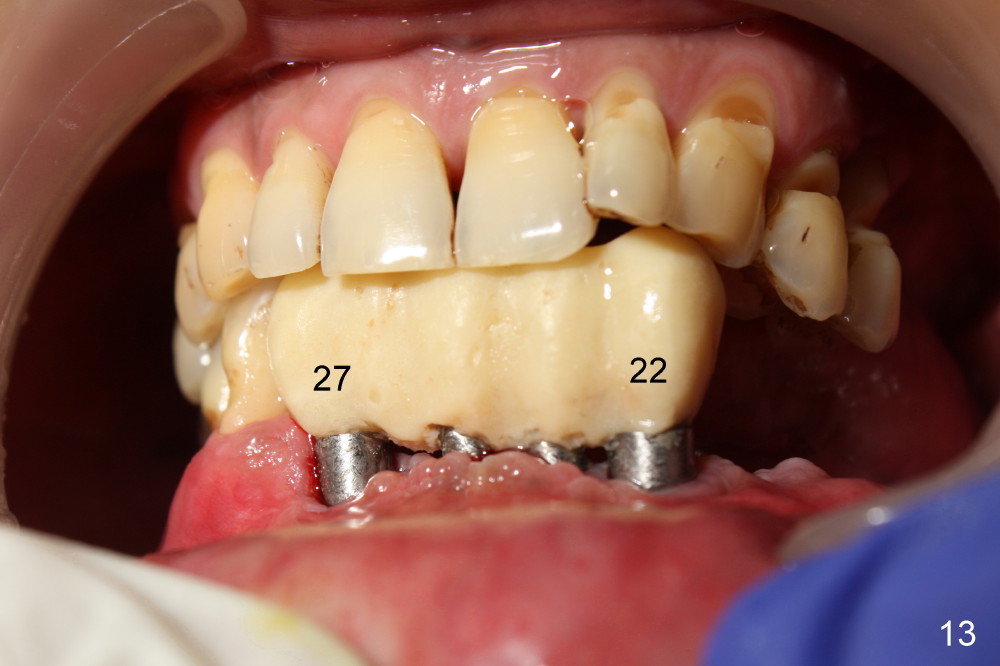

The rough surface of the implants at the sites of #22 and 27 is covered by the gingiva 2 months postop(Fig.13, as compared to Fig.10).

The 4 anterior implants appear to have been osteointegrated 5 months postop (Fig.14,15). More gingiva has covered the top portion of the implants (Fig.16). Ball abutments are placed for an overdenture (Fig.17).